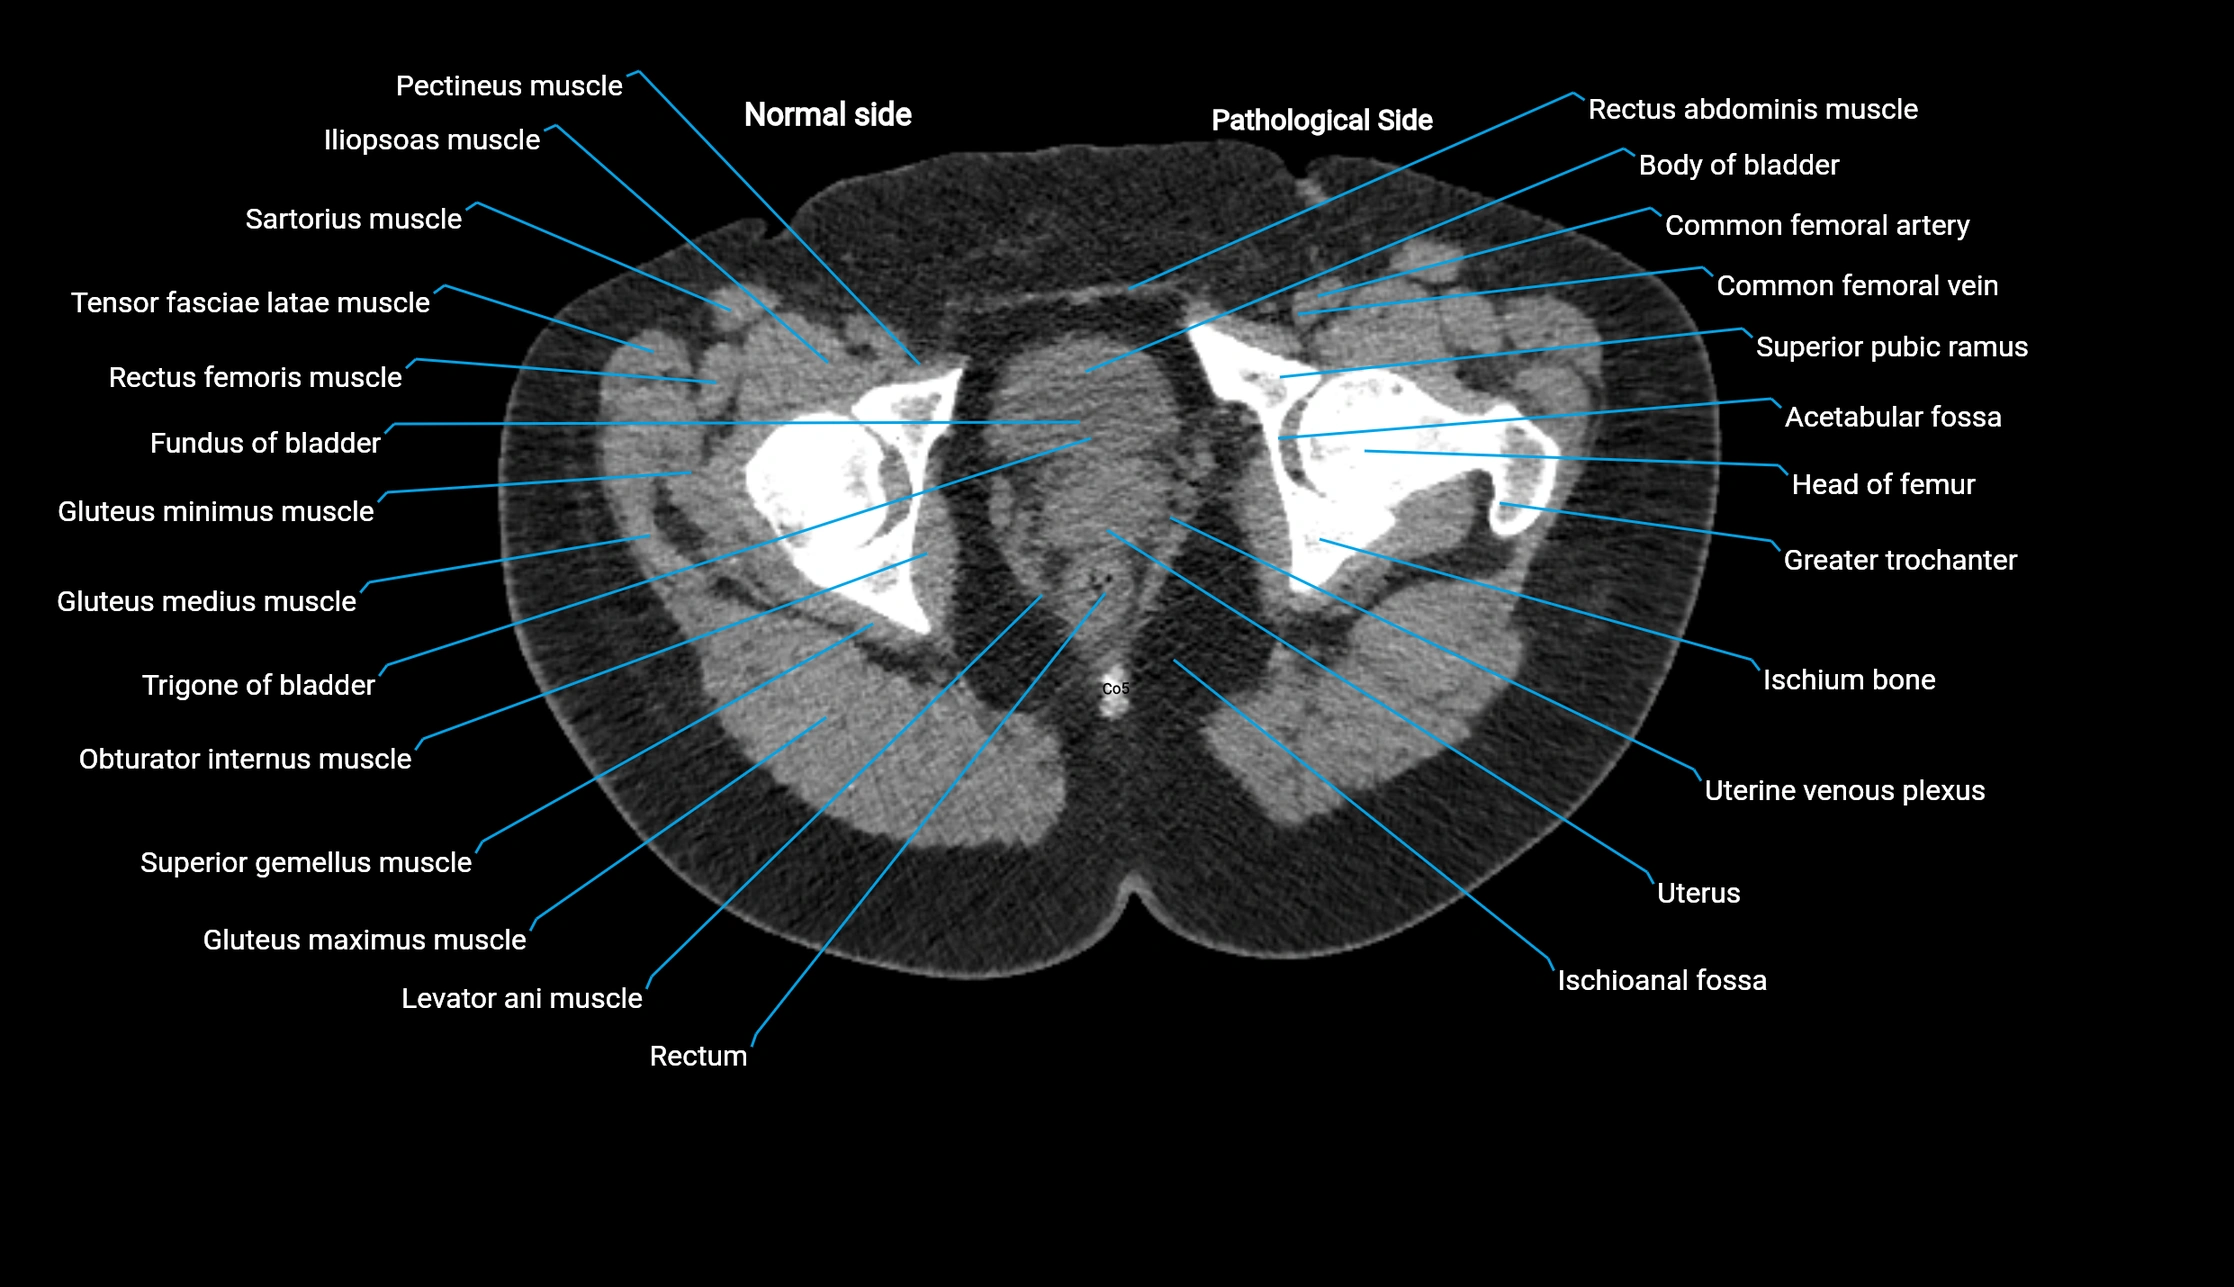

CT image

image